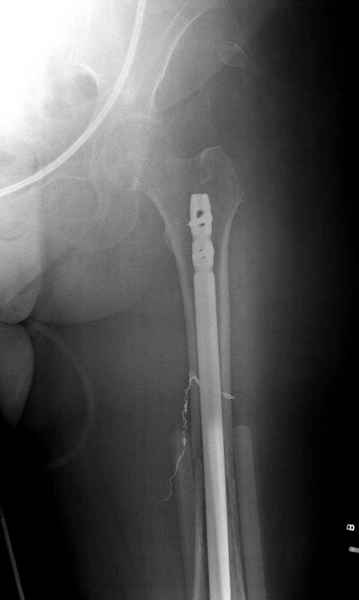

Здесь случай 66 летней пациентки со спонтанными болями в левой нижней конечности, обратилась в приемное, сделаны снимки бедра и КТ.

Патологический перелом бедра, конечность на вытяжении.

Со слов, больная ничем не болела, только последние 3 месяцев чувствовала боли в бедренной области. КТ брюшной полости подтвердил увеличенную правую почку. (5-6)

Для предупреждения кровотечения во время рассверливания, за день до операции провели эмболизацию сосудов питающий метастаз. http://radiology.rsnajnls.org/cgi/reprint/150/3/673.pdf (7-11, 12-15-16)

С минимальным рассверливанием и ретроградным методом провели остеосинтез бедра 12 мм гвоздем. (17-20)